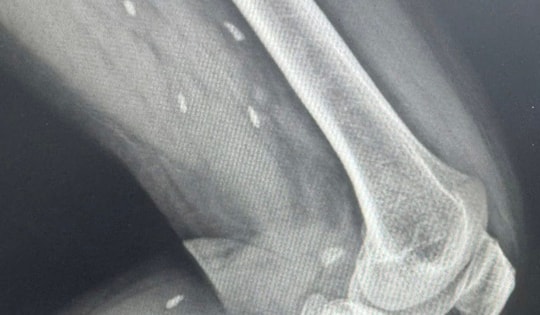

Phát hiện nhiều kén sán ở chân bệnh nhân do một thói quen thường gặp

Tiến hành chụp X- quang, bác sĩ phát hiện các mô vùng xương đùi và cẳng chân bệnh nhân có nhiều kén sán kích thước như hạt gạo.